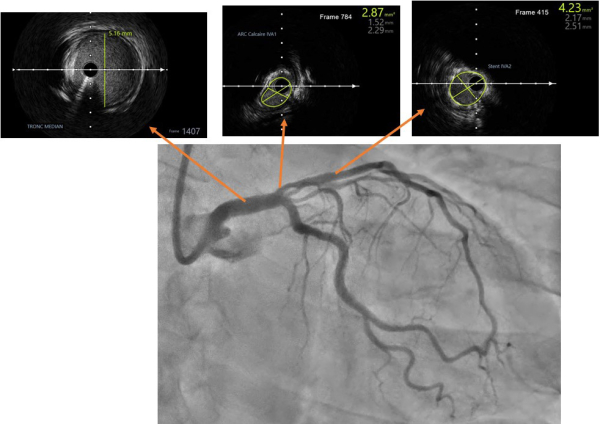

Une évaluation des lésions par imagerie endocoronaire par IVUS (Intravascular Ultra Sound-BOSTON SCIENTIFIC) (Figure 1) (Vidéo 2) est réalisée pour :

- Déterminer plus précisément les caractéristiques de cette néo lésion (longueur, calcifications) en amont du stent IVA et l’existence ou non d’une zone d’atterrissage sur l’IVA

- Aider au « sizing » du tronc commun et de l’IVA

Figure 1 : extraits des acquisitions IVUS pré angioplastie

Vidéo 2 : run IVUS pré angioplastie

Interprétation des images :

Le diamètre artériel est mesuré :

- à 2.5 mm sur l’IVA moyenne, intrastent (légère sous expansion, diamètre du stent à 2.75mm).

- et 5 mm sur le tronc commun.

- l’imagerie permet également de caractériser la lésion IVA 1 avec la visualisation d’une épine calcaire non circonférentielle du tronc commun distal vers l’IVA entre 9h et 12h responsable d’une sténose avec une surface minimale estimée à 2.8 cm² pour un diamètre minimal estimé à 1.5 mm. Le diamètre initial de l’artère est mesuré à 3 mm.